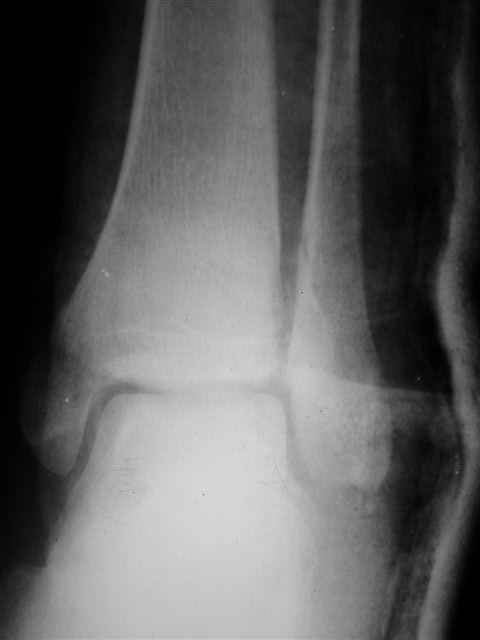

> интересуюсь тактикой лечения повреждений голеностопного сустава.

Я предупреждал, что ничего сверхъестественного. Каюсь, что одна из спиц прошла несколько дальше, чем нужно было, но главное - перелом стабилизирован и больной работает суставом в полном объёме, несмотря на представленную раннее травму коленного сустава.